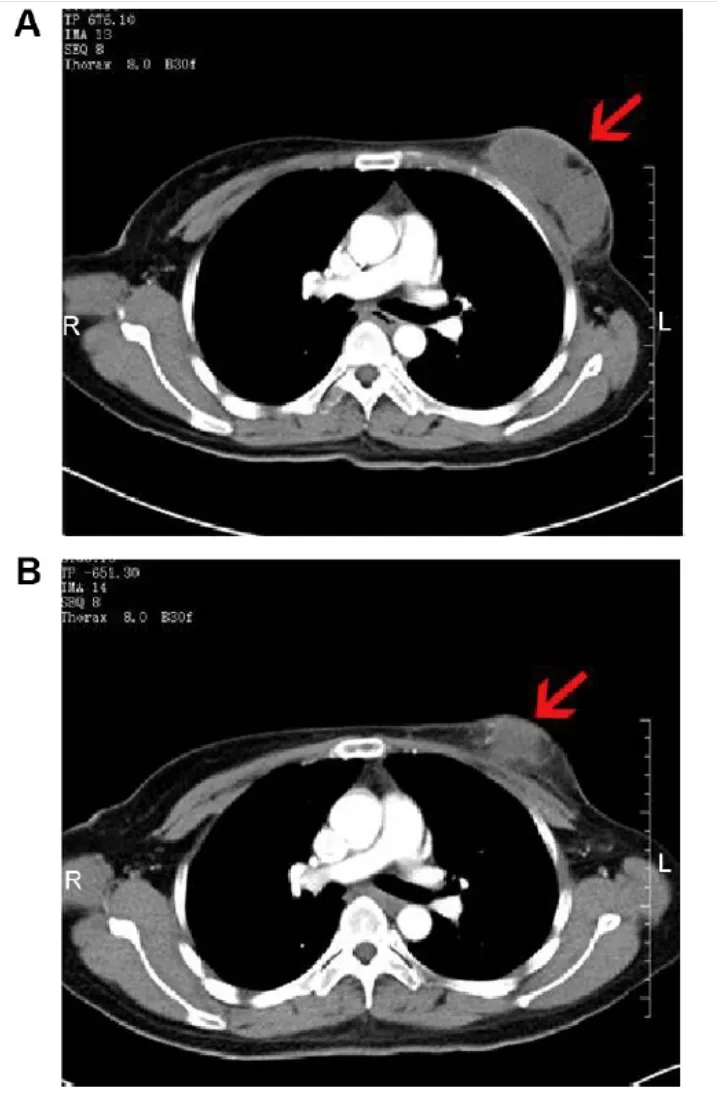

典型病例中,一位68岁女性患者治疗90天后,肺内肿瘤明显缩小;另一例57岁男性患者同样达到部分缓解(PR),肿块显著缩小。

图片来源:JCI,版权归原作者所有

这一方案被誉为晚期肺癌的“黄金组合”,不仅提高客观缓解率,还显著延长患者生存,是免疫联合治疗的重要方向。